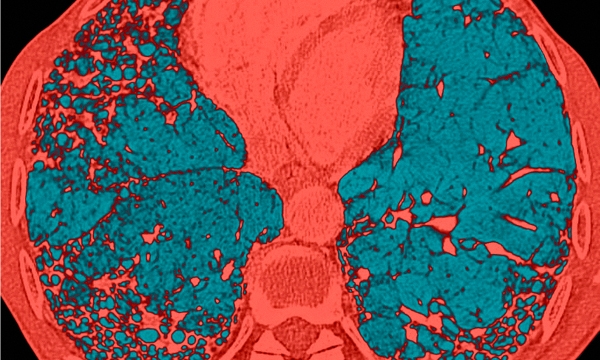

Managing idiopathic pulmonary fibrosis, a life-limiting interstitial lung disease

Managing idiopathic pulmonary fibrosis, a life-limiting interstitial lung disease

Managing idiopathic pulmonary fibrosis, a life-limiting interstitial lung disease